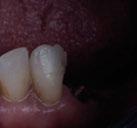

Imagen cedida por la Dra. Clara Garcete, profesora de Grado y Máster de la Universidad CEU San Pablo.

Imagen cedida por la Dra. Clara Garcete, en Clínica Ciro.